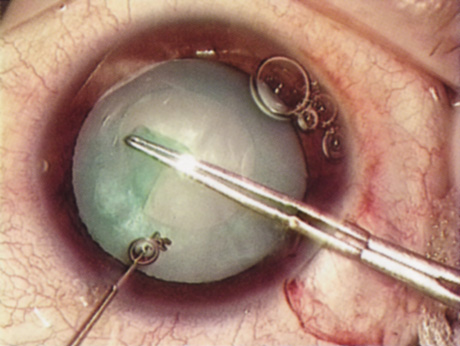

HYDRODISSECTION Hydrodissection can be performed after the surgeon has successfully completed capsulorrhexis.97 If the capsulorrhexis is not intact, fluid forced around the interior of the capsule may cause the bag to splay open. With capsulorrhexis, hydrodissection is a safe and extremely useful maneuver. Hydrodissection can be thought of as two maneuvers: hydrodelineation and cortical cleaving hydrodissection. By placing a 27-gauge cannula on a syringe filled with balanced saline solution (BSS), the surgeon can direct fluid beneath the residual anterior capsular rim to create a cleavage plane. Depending on the direction the fluid wave takes, different lamellae of the cataract will be separated. Hydrodelineation is the term used when the cleavage plane separates the adult nucleus from the fetal nucleus or the adult nucleus from the more peripheral epinucleus. Hydrodelineation often results in the characteristic golden ring sign (Fig. 11). Cortical cleavage occurs when the cortex is separated from the capsular bag (Fig. 12). Finding the cortical cleavage plane may be facilitated by gently lifting the capsular margin away from the cortex with the BSS cannula before injecting. Several small bursts of fluid allow the surgeon to monitor progress of the fluid wave. When dealing with a soft nucleus, the authors strive to perform true cortical cleaving hydrodissection. For a hard nucleus, hydrodelineation allows manipulation of less of the nuclear bulk, although the remaining epinuclear shell must be addressed in an additional step. Hydrodelineation is particularly useful if the nucleus is not freely mobile after cortical cleaving hydrodissection.